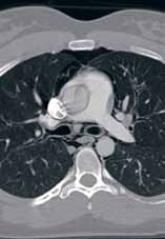

ArticleCase Report: Sudden Chest Pain Following an Asthma AttackAuthor:Major Christopher M. Howell, DSc, MPAS, PA-C, MBAPublish date: May 1, 2015 A 20-year-old woman who smokes cigarettes and has a history of childhood asthma presented with symptoms of an upper respiratory infection and diff...Read More